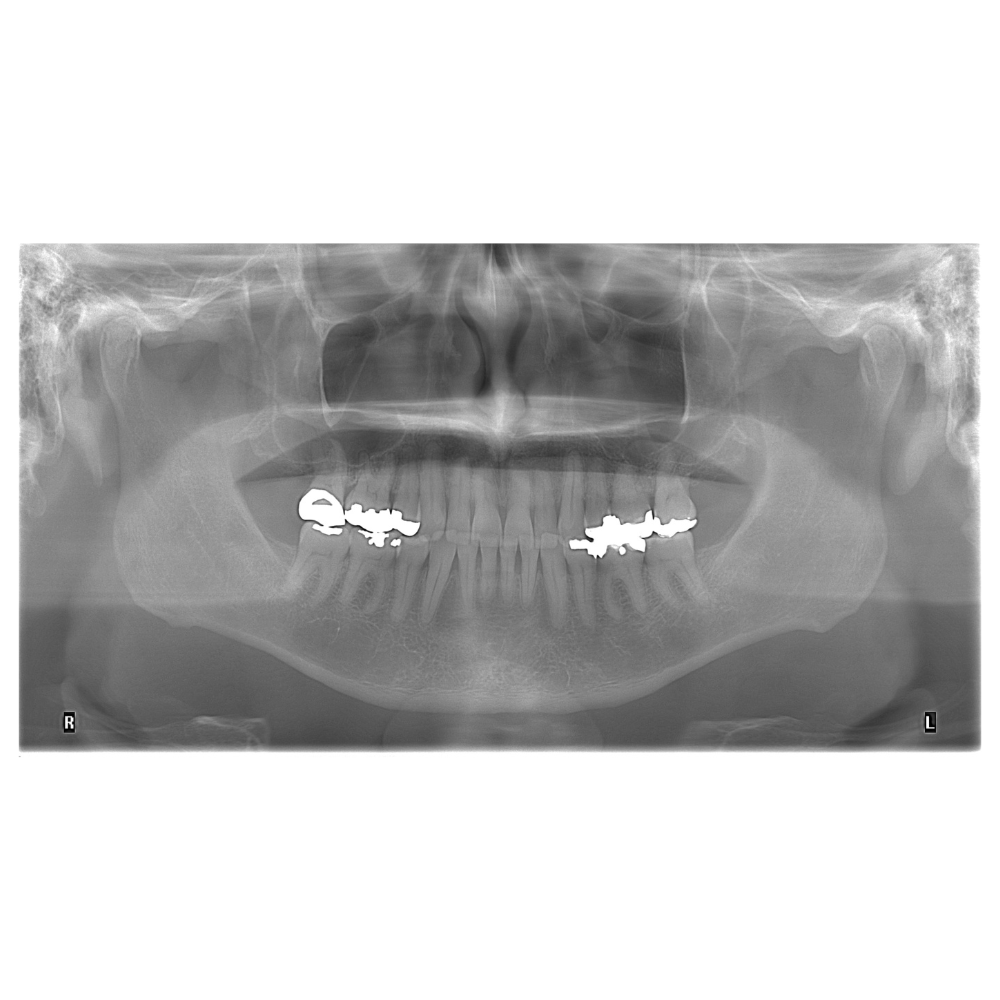

Análisis de la articulación temporomandibular

Radiografía en vista antero posterior